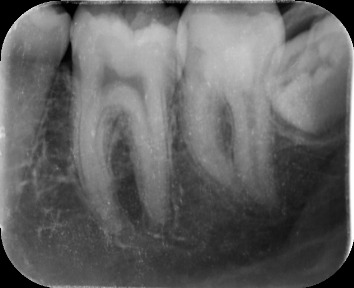

Methods: A 16 year old girl presented with bilateral carious mandibular second molars. She had symptoms of irreversible pulpitis in both the teeth. Parents refused extractuions and were reluctant to proceed with root canal therapy. After informed consent Biodentine Pulpotomy was attempted on both teeth followed by permanent composite resin restorations.

Results: The patient became asymptomatic in both teeth after the procedure. Vital radicular pulp was preserved and root canal treatment avoided